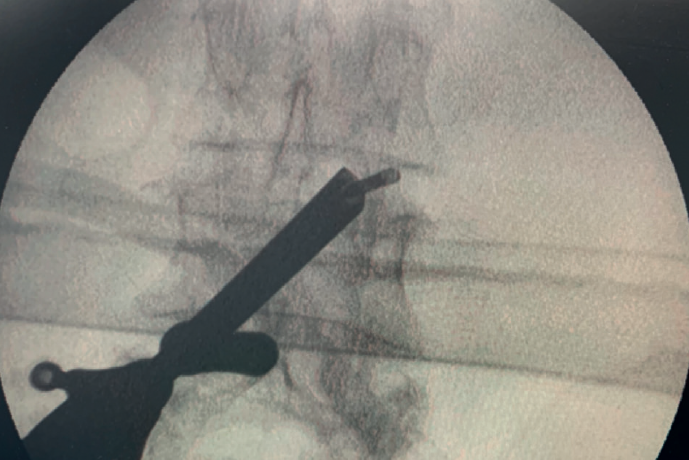

reaca.30380.fs2209015-figura8.png

Figura 8. Imagen radiológica intraoperatoria de endoscopia interlaminar uniportal ipsilateral. En esta técnica, inicialmente se descartó la opción de explorar el foramen de conjunción (lo que en técnica abierta exige la artrectomía); con el desarrollo de la técnica, también explorar el foramen ha sido posible técnicamente.